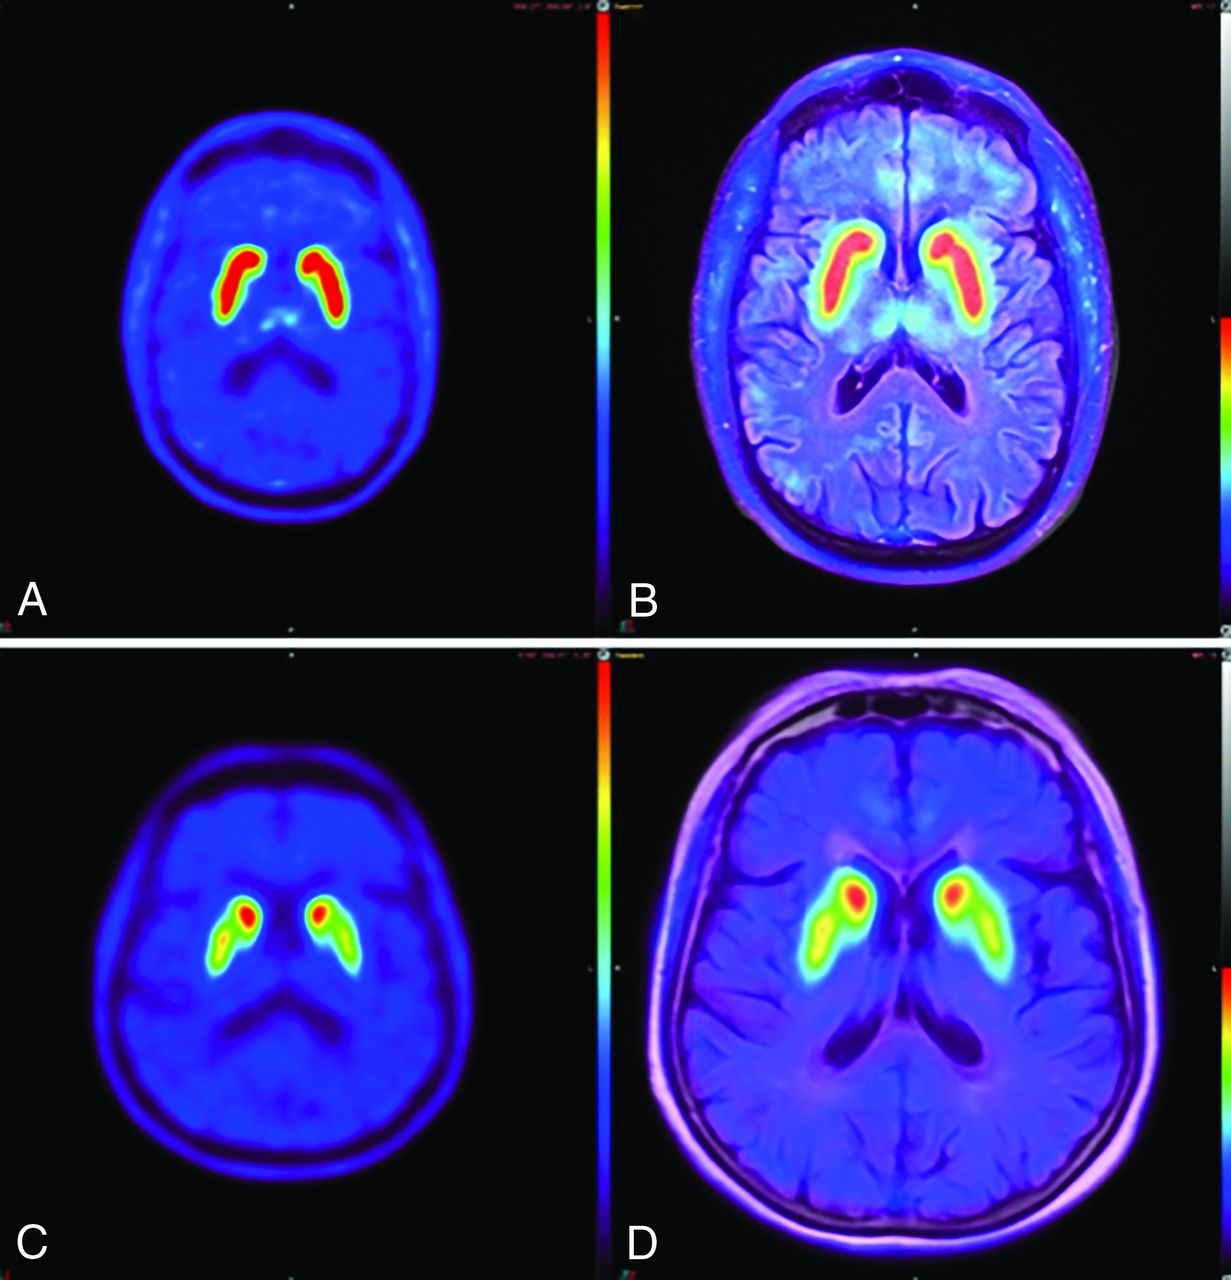

Per the neuroradiologist’s expert read, 10 studies (50%) had abnormal findings as evaluated at the standard 20-minute acquisition time (Fig 1). There was no association between reader confidence and acquisition time (reader 1, ρ = –0.13, P = .250; reader 2, ρ = –0.19, P = .100). However, image-quality ratings were lower among images with shorter acquisition times for both reviewers (reader 1, ρ = 0.23, P = .044; reader 2, ρ = 0.24, P = .036) (Figs 2 and 3).

[18F]-FDOPA brain PET and fused [18F]-FDOPA brain PET/MR imaging at a standard 20-minute acquisition time. The healthy subject (A and B) demonstrates the characteristic “comma sign” uptake in the striatum. The subject with abnormal findings (C and D) demonstrates marked loss of uptake in the bilateral striatum, particularly involving the bilateral putamina and left > right caudate nuclei, corresponding to more extensive right-sided clinical deficits.